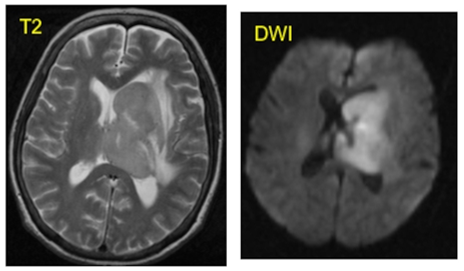

5.3. Диффузионно-взвешенные изображения, карты ИКД (DWI, ADC)

Диффузионно-взвешенные изображения (ДВИ, Diffusion Weighted Imaging, DWI) – метод визуализации броуновского движения молекул воды в тканях, основанный на различиях в движении молекул, в первую очередь, во внеклеточном пространстве. Диффузионные серии являются функциональным видом исследований, т.к. акцентируют не на общей структуре всех тканей зоны исследования, а на динамических характеристиках молекул воды. Для ряда патологий данные серии входят в рекомендованные регламенты диагностики и лечения, например, рака предстательной железы, опухоли молочной железы и др.

DWI обычно выполняют с уменьшенной матрицей К-пространства, поэтому и сами изображения чаще всего меньше по размерам и по разрешению, чем анатомические серии.

Получение DWI основано на Т2-взвешенной серии с ИП типа спинового эха. Регистрация эхо-сигнала часто осуществляется с помощью технологий EPI (Echo Planar Imaging, см. далее), но в некоторых случаях нужен и используется nonEPI-DWI с дополнительными методами типа FOCUS, MUSE или без них.

Для формирования DWI в ИП включаются два дополнительных диффузионных градиентных импульса, которые подаются перед и после первого 180°-сигнала вдоль определенных направлений (X, Y, Z или промежуточные). Регистрируемый сигнал зависит от степени подвижности молекул воды в исследуемой области и параметров градиентных импульсов. Максимальная интенсивность сигнала будет наблюдаться для молекул воды с низкой подвижностью, т. е. с ограниченной диффузией, т.к. возбужденные протоны не успевают «разбежаться» [6].

Параметры градиентных импульсов (амплитуды, длительности, время между ними) настраиваются так, чтобы выделять диффузию определенной скорости. Обобщением этих параметров является b-фактор (b-value) – чем он выше, тем более высок вклад диффузии в контраст изображений, т.е. осуществляется взвешивание по этому свойству. Но, вместе с тем, при возрастании b-фактора снижается интенсивность сигнала. b-фактор равный нулю дает анатомическую Т2-серию со сниженным разрешением и с подавлением сигнала от жировой ткани.

Для диагностики опухолей обычно используется высокий b-фактор (больше 1000, оптимально больше или равно 1400), который позволяет обнаружить сниженную диффузию в местах, где клеточная плотность аномально увеличена, а объем внеклеточной жидкости уменьшен. При меньшем b-факторе диффузионного взвешивания недостаточно для обнаружения таких аномальных зон, т.к. начинает преобладать Т2-взвешивание (эффект Т2-просвечивания). Это выражается в зонах высокого сигнала там, где ограничения диффузии на самом деле нет.

Измеряемый коэффициент диффузии (ИКД, Apparent Diffusion Coefficient, ADC) – аналитическая количественная характеристика, разработанная для того, чтобы снизить влияние Т2 на контраст. Изображения ADC не формируются путем сканирования, а рассчитываются по одной DWI-серии, как правило, для двух разных b-факторов, и имеют такой же размер, как ее 3D-объем.

Интерпретация ADC-изображений условно обратная DWI – чем сильнее ограничена диффузия, тем ниже сигнал на ADC. Совместное использование DWI и ADC позволяет более точно определять зоны действительного ограничения диффузии, без эффектов Т2-просвечивания.